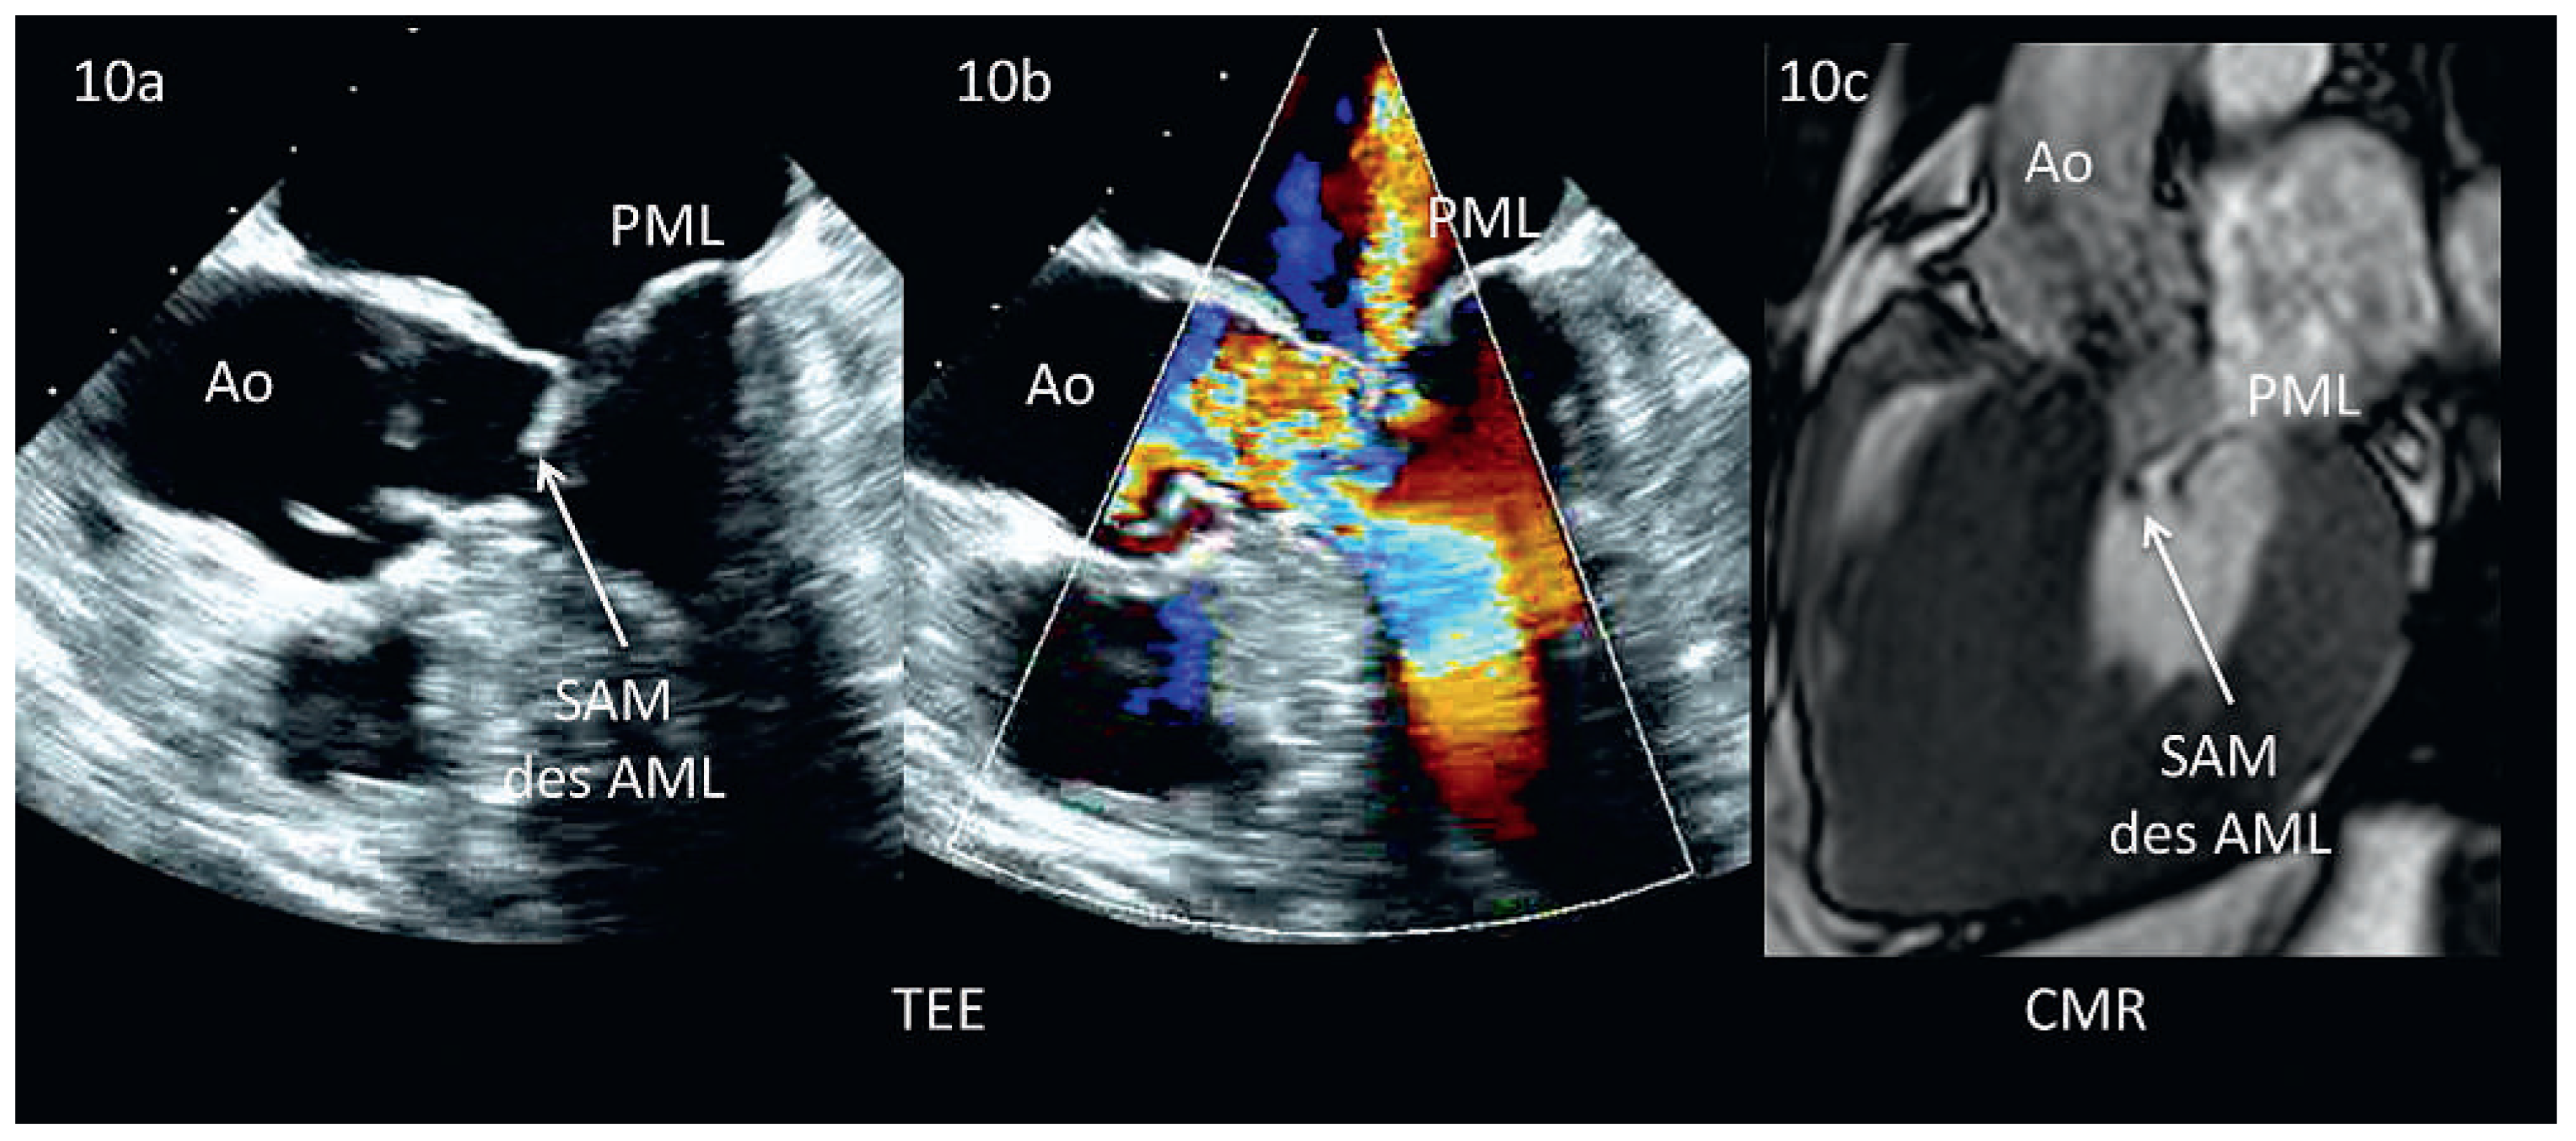

Abbildung 10. Überschrift: Hypertrophe obstruktive Kardiomyopathie, Vergleich TEE und CMR. Abb. 10a: Im TEE dargestellte systolic anterior motion des anterioren Mitralklappensegels (SAM). Mittels Farb-Doppler kann die Flussbeschleunigung im LVOT infolge SAM sowie der typische, nach posterior gerichtete Jet visualisiert werden (Abb. 10b). Abb. 10c: Neben dem SAM ist insbesondere das Ausmass der Hypertrophie erkennbar (Patient nicht identisch). Abkürzungen: Ao = Aorta, AML = anteriores Mitralsegel, PML = posteriores Mitralsegel, SAM = Systolic Anterior Motion.

Die 2D TTE stellt die Methode der Wahl dar zur Diagnose oder zum Ausschluss einer HOCM. Nicht nur können die Wanddicken meist sehr adäquat gemessen werden, vielmehr ermöglicht die M-Mode-Echokardiographie die Darstellung des SAM aufgrund seiner ungeschlagenen zeitlichen Auflösung. Zur Diagnose einer relevanten Obstruktion bei HOCM eignet sich der CW-Doppler zur Bestimmung des Druckgradienten über dem linksventrikulären Ausflusstrakt (LVOT) oder innerhalb des Ventrikels. Besonders interessant und diagnostisch wichtig sind dabei die hämodynamischen Veränderungen (s. Abbildung 10a und b) während gewissen Manövern wie Valsalva oder dem sogenannten‚ leg-rise’-Test. Die Echokardiographie ist auch bei der Therapie der HOCM essenziell: Bei der septalen Alkoholablation kann sie durch Injektion von Kontrastmittel in den entsprechenden Koronarast das zu abladierende Gebiet darstellen und unmittelbar nach Ablation den Therapie-Erfolg messen (Rückgang der LVOT-Obstruktion und damit Rückgang der Mitralinsuffizienz). Bei der chirurgischen Resektion erlaubt die perioperative TEE die exakte septale Ausmessung vor der Myektomie.

Die CMR gehört zur Routinediagnostik bei HOCM. Dies allerdings weniger, um die Mitralinsuffizienz zu quantifizieren, als vielmehr das exakte Ausmass und die Lokalisation der Hypertrophie aufzuzeigen. Zudem kann der Fibroseanteil am Myokardgewebe mittels Late-Gadolinium-Enhancement (LGE) quantifiziert werden. [45]. Die Cine-CHR erlaubt eine hervorragende Beurteilung der SAM (s. Abbildung 10c) [12,44]. Zusätzlich kann die Phasenkontrast-Flussmessung den Druckgradienten über dem LVOT und damit den Schweregrad der Obstruktion beurteilen; diese ist jedoch aufgrund der zeitlichen Auflösung der Echokardiographie unterlegen.